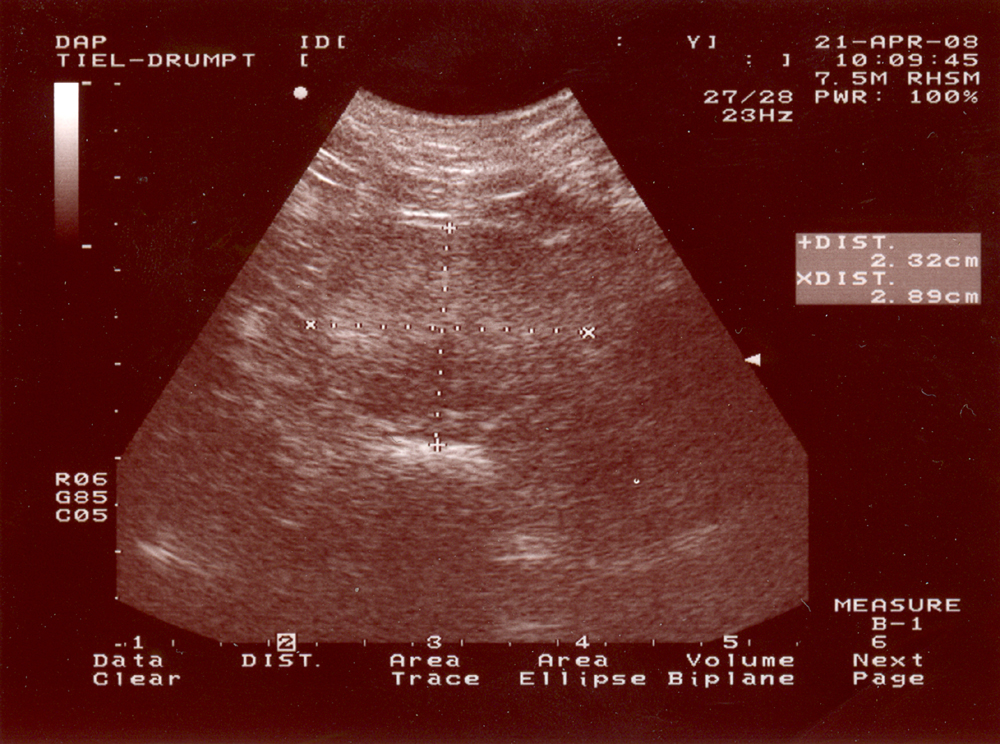

Zoals aangegeven groeit de prostaat onder invloed van testosteron. Hierdoor wordt verklaard dat bij sommige hypersexuele dieren de prostaat onevenredig groot kan worden. Meestal zien we dit bij oudere, ongecastreerde reuen. Klachten die kunnen optreden zijn bijvoorbeeld dat de hond moeilijk kan poepen of wel eens wat druppeltjes vocht verliest onafhankelijk van het plassen. Soms vertoont een dier helemaal geen klachten bij deze afwijking. In sommige gevallen kan de dierenarts de prostaat rectaal voelen en beoordelen of de prostaat inderdaad vergroot is. In andere gevallen is een echo nodig om de prostaat in beeld te brengen. Een echo geeft zowiezo meer informatie over de aard van de vergroting.

Een prostaatinfectie kan op een aantal manieren ontstaan. Omdat de blaas en prostaat door de plasbuis verbonden zijn kan een bacteriële blaasontsteking tot een prostaatinfectie leiden (andersom kan een prostaatinfectie een blaasinfectie tot gevolg hebben). Vaak is een prostaat gevoeliger voor infectie als hij al vergroot is. Als de prostaat geinfecteerd is, kan uw hond daar goed ziek van zijn. Het kan u bijvoorbeeld opvallen dat hij pijnlijk is bij het plassen. Bij een rectaal onderzoek zal het dan ook pijnlijk zijn om de prostaat aan te raken. Soms kan het nodig zijn om een echo te maken en/of wat prostaatvocht af te nemen om te kijken of er inderdaad sprake is van een ontsteking. Indien een prostaatinfectie wordt vastgesteld zal meestal met antibiotica moeten worden behandeld.

In een heel enkel geval is er sprake van kanker in de prostaat. Deze aandoening is vrijwel altijd kwaadaardig en kan erg slecht worden behandeld. Doordat het gezwel op de plasbuis kan gaan drukken kan uw hond bijvoorbeeld steeds moeilijker plassen of poepen. De diagnose wordt gesteld doordat er onder echobegeleiding een monster van de prostaat wordt afgenomen en opgestuurd voor beoordeling door een patholoog.